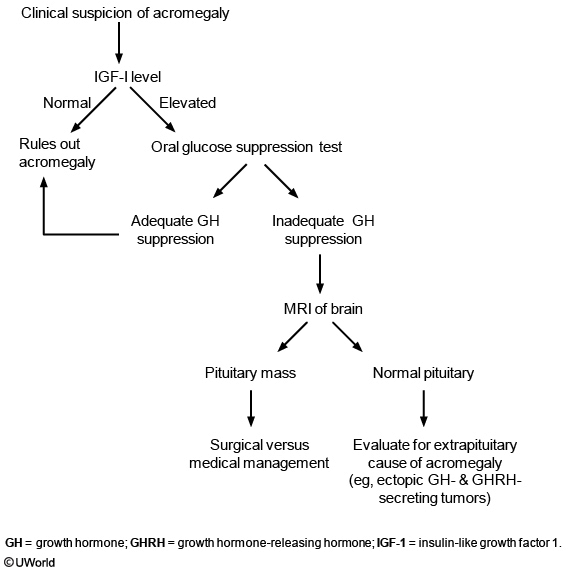

if acromegaly is suspected, what do you measure?

igf-1

it is consistenly elevated throughout the day while gh fluctuates (low sens/spec)